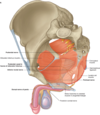

What are the walls of the pelvic cavity and what does each one contain?

Lateral wall (1)

- “hip bones”

- Obturator m, n, a, v

Anterior walls (2)

- pubic bones and pubic symphasis

Posterior wall (3)

- sacrum and coccyx

- sacroiliac joints

- sacrial plexus

- periform plexus

Floor (4)

- pelvic diaphragm

Obturator internus

- Medial surface of obturator membrane–> leave true pelvis through the lesser sciatic foramen –> (turn 90 degrees) freater trochanter of femur

- nerve to obturator internus (L5-S2)

- lateral/ external rotation of hip

**in lateral wall of the pelvis**

Piriformis

- leaves the pelivs through the greater sciatic formen–> insert on femur

- S1-S2

- external/ lateral rotation of the hip

bed for the nerves of the sacral plexus

posterial pelvic wall

- What does the pelvic floor do?

- What does it include on the bottom?

- what makes this up?

- sling that supports the abdominopelivic viscera. and it resist in intra-abdomincal pressure

- Pelvic diaphragm

- Levator ani muscles (green)

- puborectalis

- pubococcygeus

- iliococcygeus

- coccygeus aka ischiococcygeus (Red)

- Levator ani muscles (green)